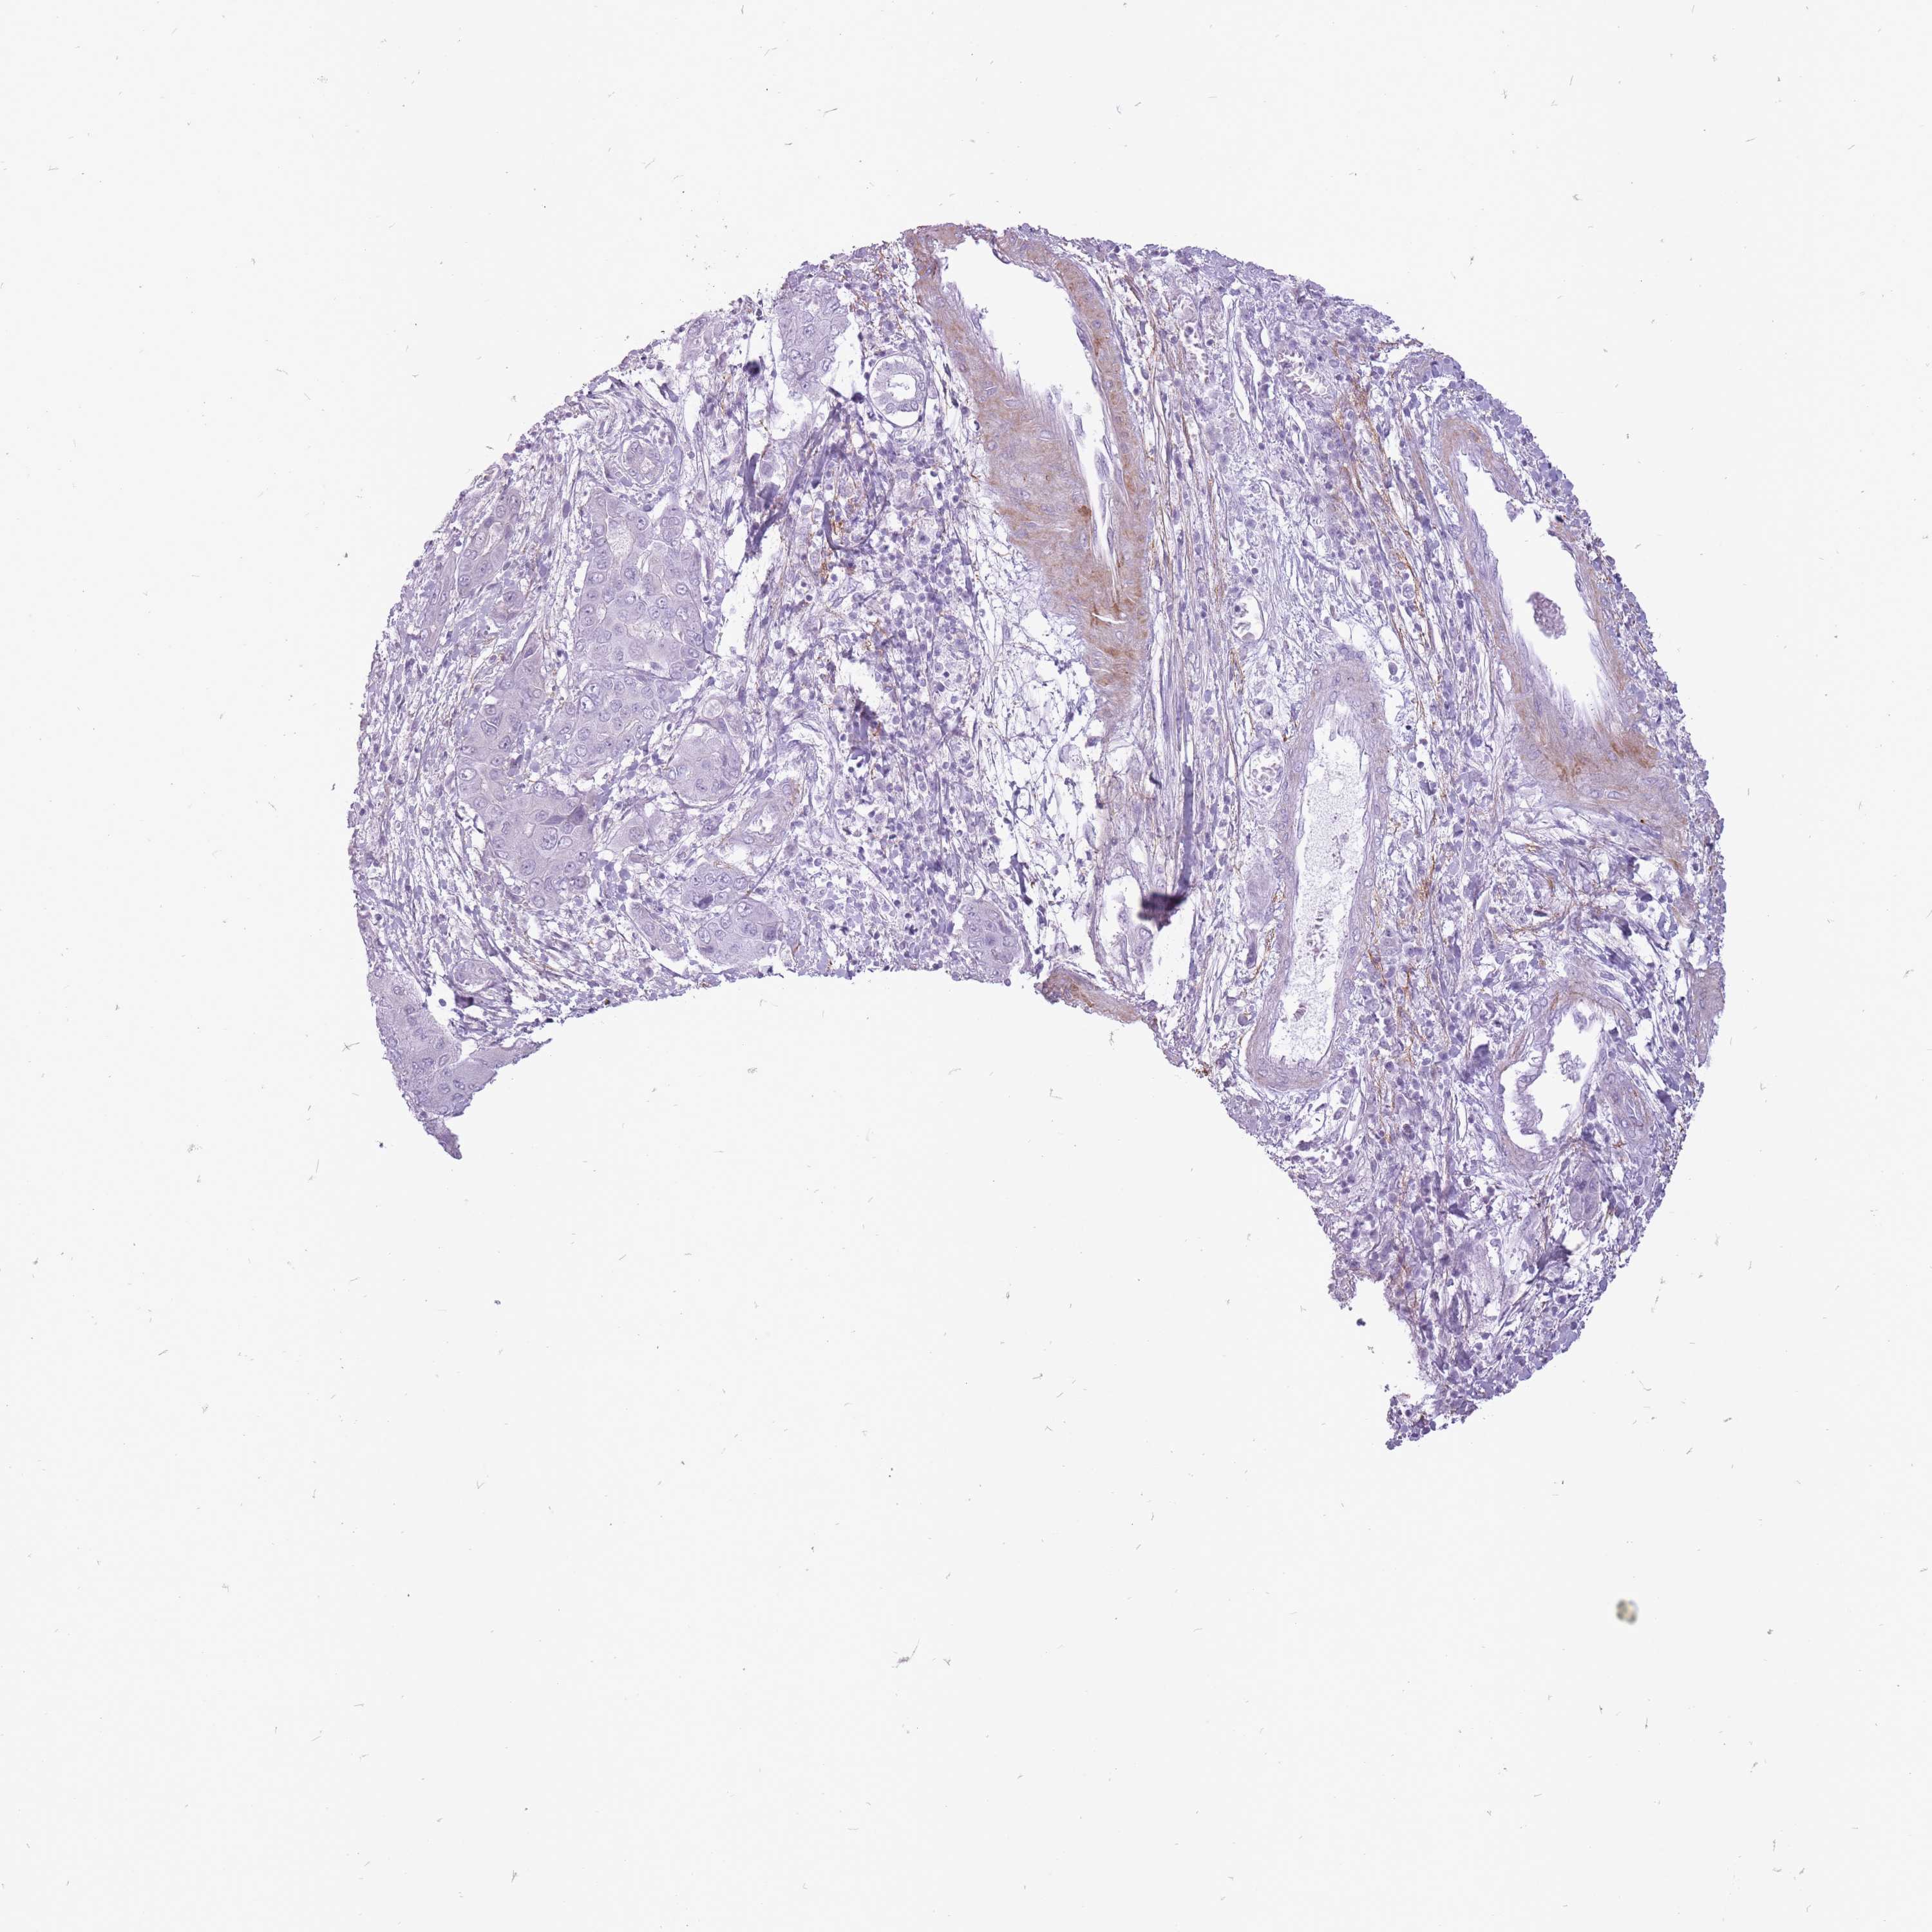

LIVER CANCER - Protein expressioni

A mouse-over function shows sample information and annotation data. Click on an image to view it in a full screen mode. Samples can be filtered based on level of antibody staining by selecting one or several of the following categories: high, medium, low and not detected. The assay and annotation is described here.

Note that samples used for immunohistochemistry by the Human Protein Atlas do not correspond to samples in the TCGA dataset.

Antibody stainingi

Antibody staining in the annotated cell types in the current human tissue is reported as not detected, low, medium, or high, based on conventional immunohistochemistry profiling in selected tissues. This score is based on the combination of the staining intensity and fraction of stained cells.

Each image is clickable and will lead to virtual microscopy that enables deeper exploration of all samples and also displays staining intensity scores, fraction scores and subcellular localization as well as patient and tissue information for each sample.

Antibody HPA050527

Staining

High

Medium

Low

Not detected

Intensity

Strong

Moderate

Weak

Negative

Quantity

>75%

75%-25%

<25%

None

Location

Nuclear

Cytoplasmic/membranous

Cytoplasmic/membranous,nuclear

Cholangiocarcinoma

Carcinoma, Hepatocellular, NOS